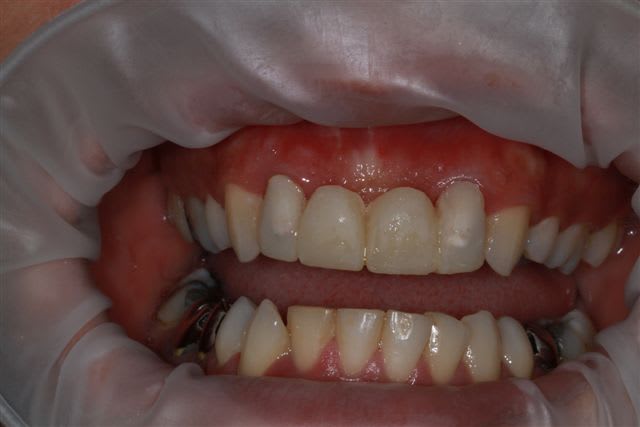

sur-traitement, pompe à fric, assassinat ...etc.. afin d'éviter tout ça je soumet à votre sagesse un cas sympa.

Patiente sympa, 30 ans, un bridge ceramo-métal fait il y a 10 ans, en fin de vie.

En réalité je sais déjà ce que je vais faire, mais implants, bridge ou pourquoi pas adjointe???

Les endo et les IC dans les 12-22 sont sublimes...et ça a durer 10 ans....incroyable...Il y a pas de la paro aussi ?